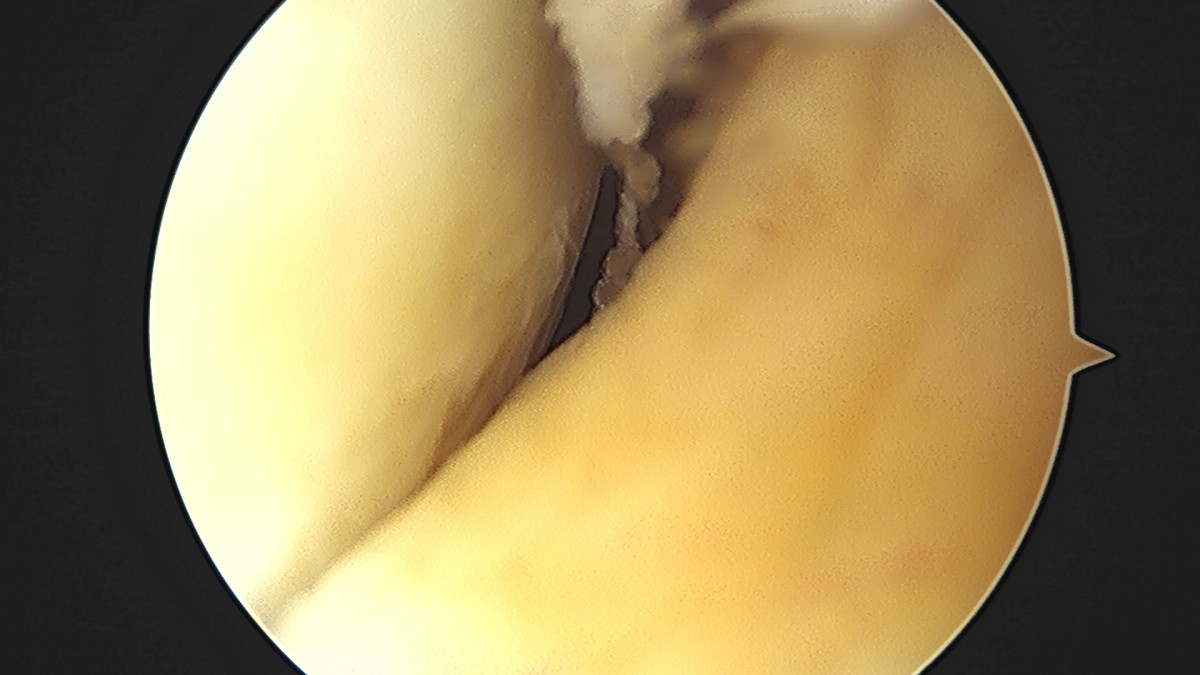

이재상원장님 무릎 전방십자인대 재건술 김태O 환자

작성자 최고관리자 댓글 0건 조회 679회 작성일 25-09-16 16:23